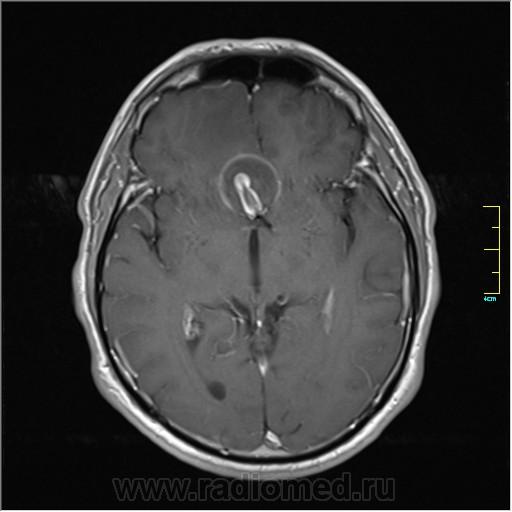

Пациентка направлена на исследование с диагнозом "Гипертонический криз", энцефалопатия неуточненная.

Post-GAD:

частично функционирующая аневризма

Иначе говоря, аневризма с хронической геморрагией, т.к. мы видим фракции крови различного возраста.

Пожалуйста!

Кстати, я этот случай выложил не только чтобы показать, но и чтобы посоветоваться. Мне именно такая картинка впервые попалась, и может быть я в чем-то не прав. Буду рад услышать ваше мнение.

По-моему, аневризма с пристеночными тромбами.

Постепенное пристеночное образование тромбов приводит к появлению типичного для аневризмы феномена -слоистости МР сигнала в полости аневризмы. Данная картина демонстрирует слоистый характер тромботических масс в полости аневризмы .Функционрирующая часть имеет низкий сигнал во всех режимах сканирования. Дополнительно-перифокальный отек.

А может более корректно интерпретировать как частично тромбированная аневризма... Уж коь речь идет о фракциях, ну то есть о тромбе по сути.... Ну и плюс перфокальный отек головного мозга (вероятнее цитотоксический+вазогенный).